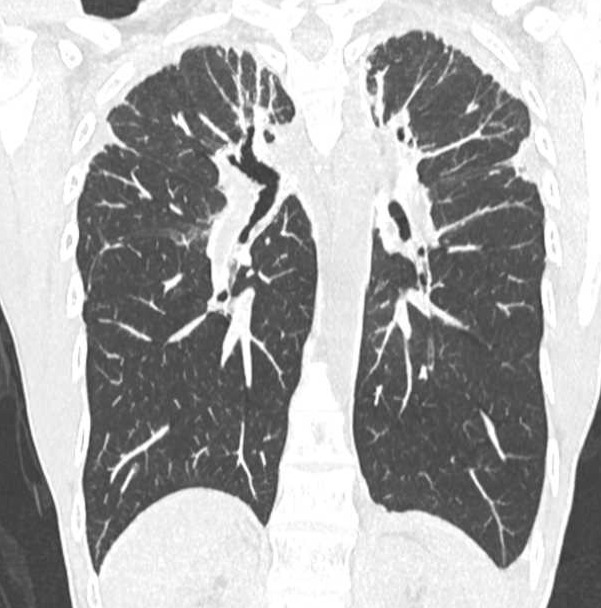

1/ 📢 Let’s talk about pleuroparenchymal fibroelastosis (PPFE)! 🔥 This rare lung disease has very characteristic CT findings, even though in most cases, we don’t really know what causes it! 😬👇🧵

1/ 📢 Let’s talk about pleuroparenchymal fibroelastosis (PPFE)! 🔥

This rare lung disease has very characteristic CT findings, even though in most cases, we don’t really know what causes it! 😬👇🧵